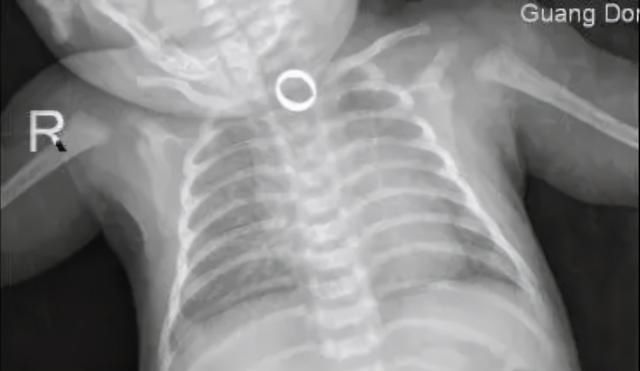

家人只好把可可送到了医院,X光检查发现,戒指就卡在食道内。满月婴儿的食道非常狭窄,仅有6~8mm,异物不仅容易堵塞在食管,还容易造成黏膜损伤。

医生争分夺秒,终于将戒指取出,小家伙也总算是转危为安了,真是差点悲剧,让人捏一把汗。